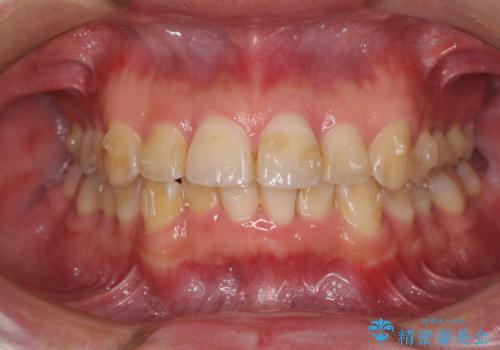

ディープバイトと叢生を解消 インビザライン矯正

- 前歯のデコボコを強い咬みしめを気にして来院された患者様です。

インビザラインを用いて、前歯の叢生を解消するとともに、ディープバイトを改善していくこととしました。

ディープバイトが改善されたことで、顎への負担が軽減され、更には上顎前歯の突出感も改善することができました。